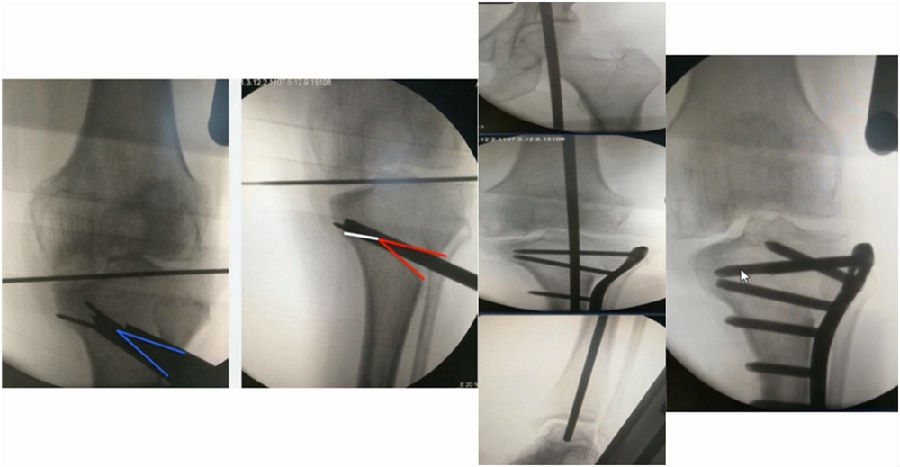

术中影像

结合影像学来看,该患者单纯用闭合截骨或开放截骨,对肢体均有影响,所以决定采用混合型截骨。术中混合截骨旋转中心选在内外1/3处,先做闭合楔,然后顺势将开放楔敲开,达到术前设计的目标力线。术后随访力线达到要求。

术后X线